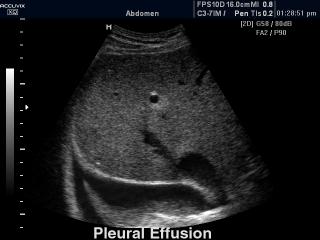

В разделе "Абдоминальные исследования" атласа представлены результаты ультразвуковых исследований органов брюшной полости. Здесь вы можете посмотреть изображения желчного пузыря, печени, почек и кишечника, эхограммы: камень в мочеточнике, внутрипеченочный кальцификат, гемангиома, спленомегалия и др.